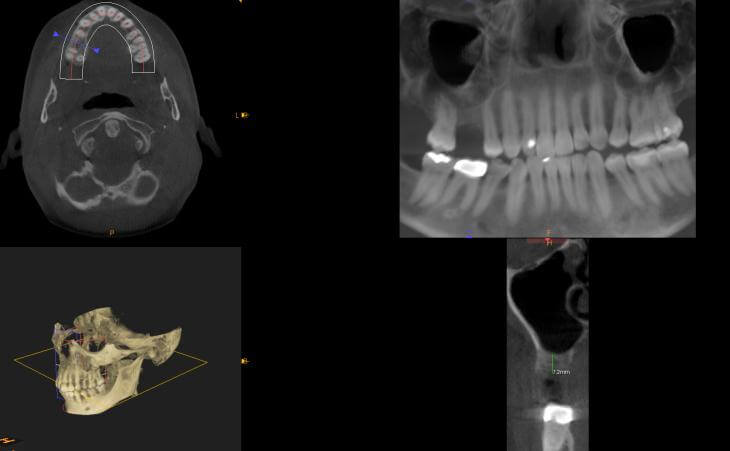

Patient lost upper right molar due to decay. Had insufficient bone for implant placement without a bone graft. Underwent Internal Sinus lIft procedure with Immediate Implant Placement

Pt presented with bone loss upper left jaw and wanted to have implants placed. A ct scan determined insufficient bone for implant placement. The patient underwear a Sinus lift procedure to regrown the lost bone.